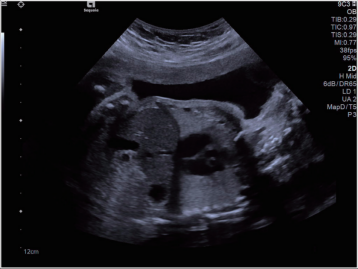

超聲

原理:超聲的原理是用超聲波穿透人體,當(dāng)聲波遇到人體組織時會產(chǎn)生反射波,通過計算反射波成像;

應(yīng)用:主要用于腹部、婦科、心臟等的檢查;

優(yōu)點:多方向觀察,實時成像;

缺點:超聲受氣體干擾大,對于腸道等含氣體較多的器官,超聲診斷準(zhǔn)確率會降低,所以一般腸道檢查使用腸鏡;

超聲圖像舉例